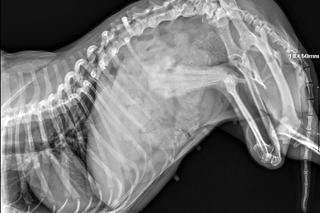

Oczom aktywistów ukazała się niewielka suczka przywiązana linką do zniszczonej, brudnej budy budą. Chociaż tego dnia było bardzo ciepło, a w naczyniach nie było wody do picia. Wokół psa latał rój much. Okazało się, że suczka dźwigała na brzuchu olbrzymi nowotwór wielkości piłki, który w kilku miejscach już zaczął pękać. Z ran wyciekała wydzielina, zwabiająca owady na żer.

- Sam guz ważył około 20% całej masy ciała psiaka. Ponadto suczka była bardzo wychudzona. Wszystko wskazywało na wielomiesięczne zaniedbania. Do tego trzeba było wdrożyć pilnie leczenie, w związku z tym fundacja natychmiastowo podjęła decyzję o odebraniu zwierzęcia właścicielom. Jednak to nie koniec historii - przekazała Fundacja Psa Karmela. Wyrwana z piekła suczka otrzymała imię Maffi.

- Edi teoretycznie dostała szansę na nowe, mniej bolesne życie, ale w praktyce niestety to zależy również od funduszy. Jej operacja została przez klinikę oszacowana na kwotę do 10 tysięcy złotych, co będzie dla nas dużym wyzwaniem. Sama tomografia komputerowa, która już się odbyła, wyniosła około 2 tysięcy. Do tego dochodzą koszty innych badań i utrzymania. To na Edi skupiła się większa uwaga, ale w tej sprawie nie zapominamy również o Maffi z nowotworem. Została przebadana, już jest po operacji a guz został usunięty, nadal jest obserwowana pod kątem przerzutów. Obecnie Maffi czuje się dobrze. Jednak jej przypadek także wiąże się z dużym kilkutysięcznym kosztem. Dla nas – małej i młodej fundacji – takie kwoty są kosmiczne, niemożliwe do pokrycia bez wsparcia dobrych ludzi, dlatego każdemu, kto zechce w ten sposób uratować z nami psiaki, jesteśmy ogromnie wdzięczni - mówi prezes Fundacji Psa Karmela, Michał Gromada, który odebrał interwencyjnie obie suczki.